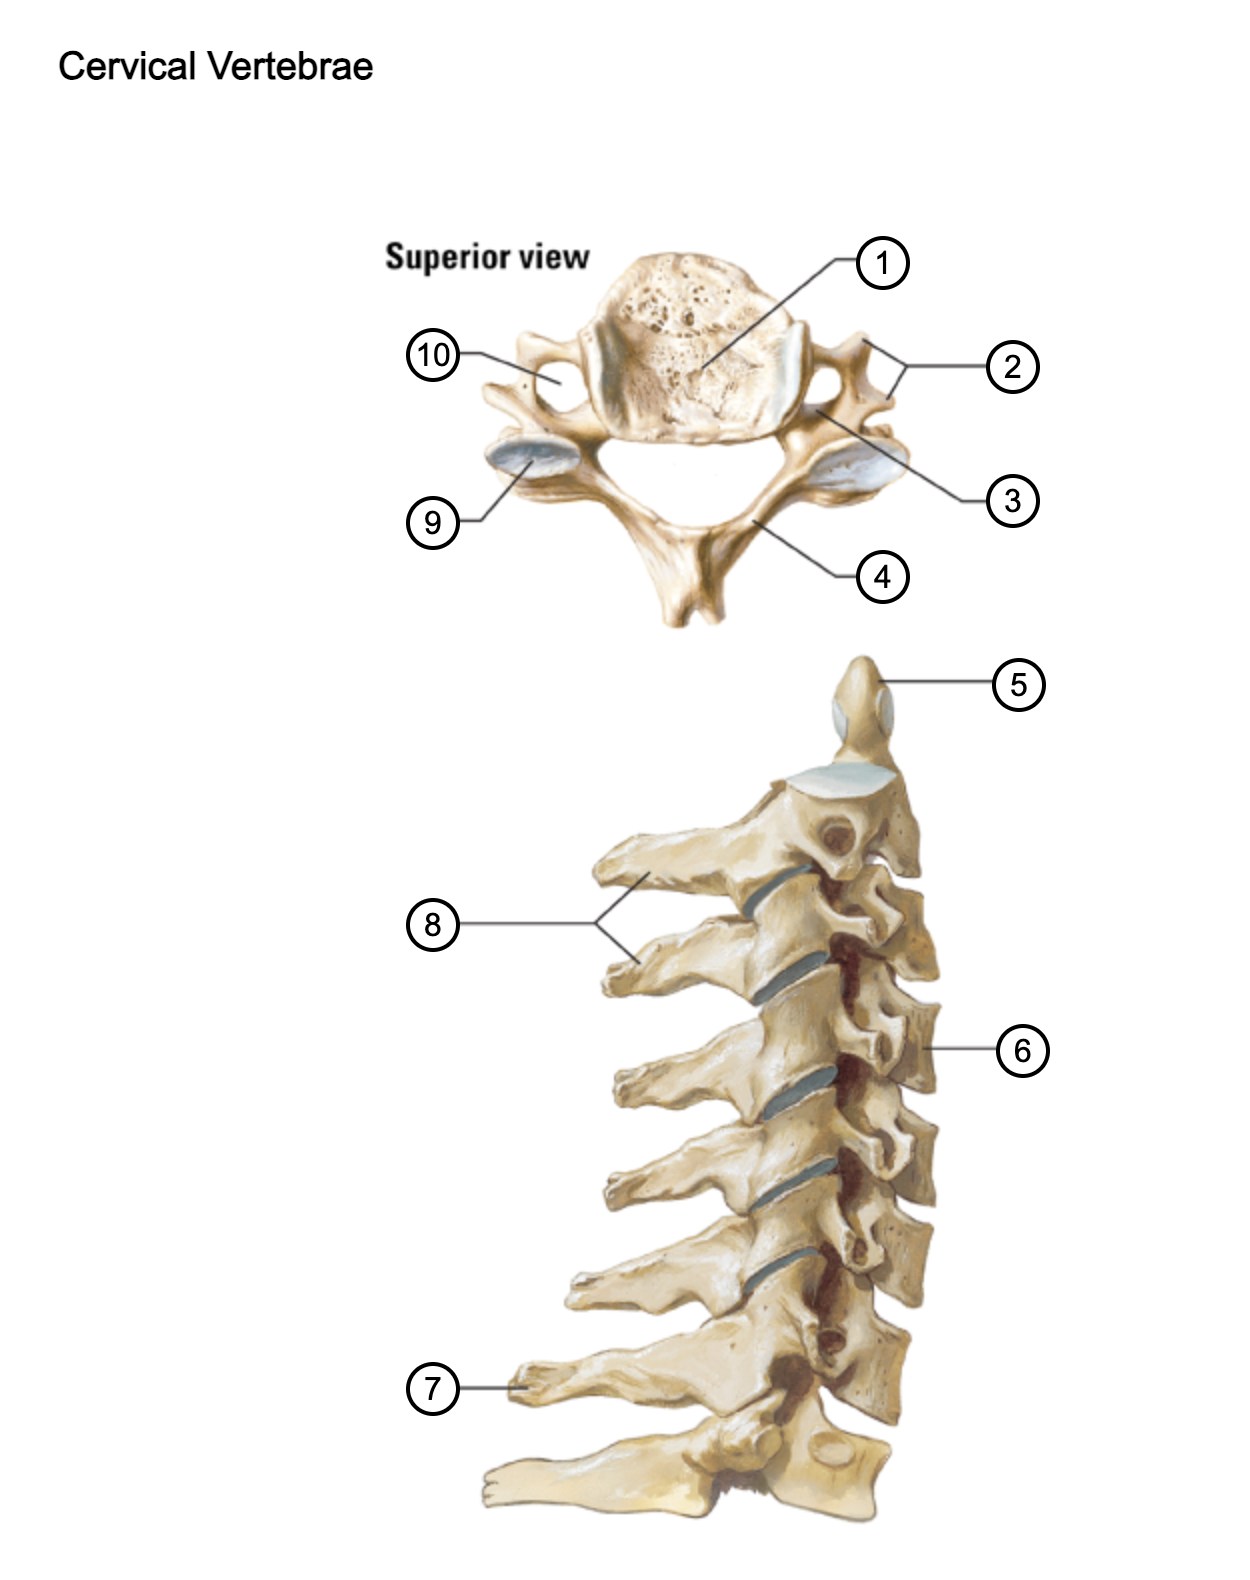

1

vertebral body

2

transverse process

3

pedicle

4

lamina

5

dens axis

6

vertebral body of C4

7

spinous process C7 (vertebra prominens)

8

spinous processes (C2 and C3)

9

superior articular process of C4

10

transverse foramen